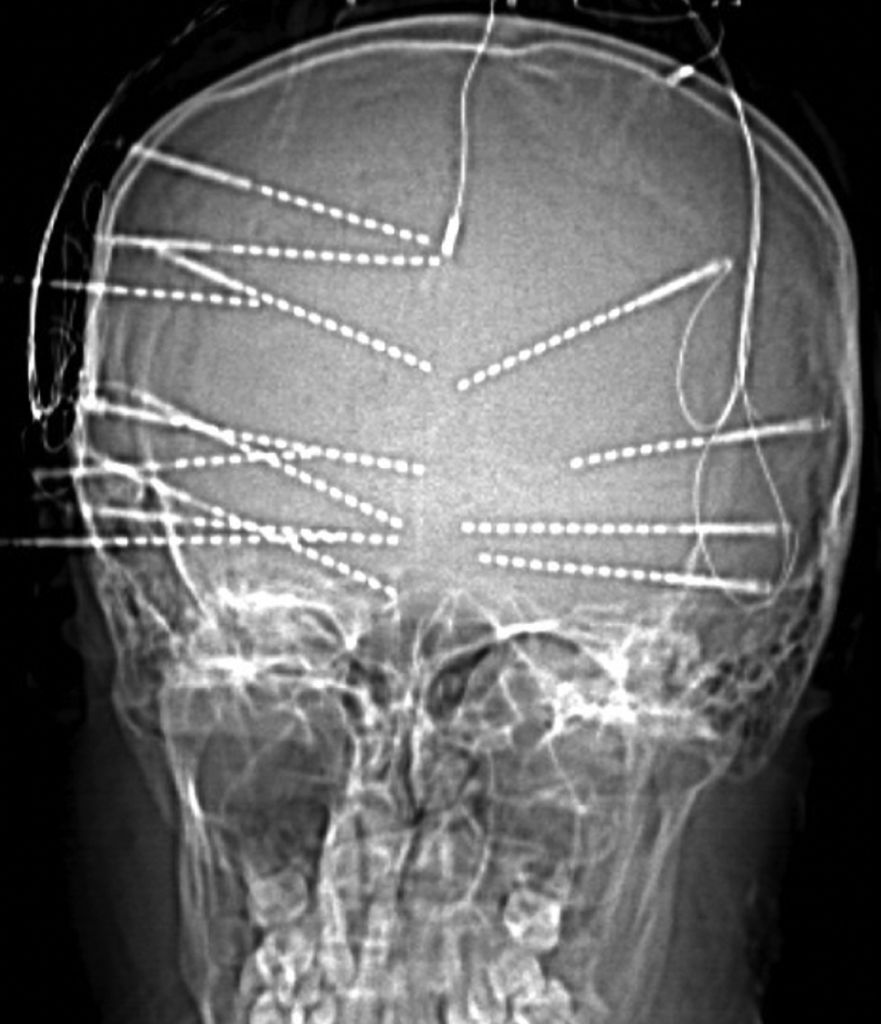

Children with epilepsy may experience a wide range of seizure types, from subtle staring spells and brief lapses in awareness to convulsive seizures involving the entire body. Ongoing seizures can interfere with learning, development, behavior, and overall quality of life, making early and accurate diagnosis essential. Comprehensive evaluation includes advanced neuroimaging, prolonged video-EEG monitoring, neuropsychological testing, and, when necessary, specialized functional studies to precisely identify the source of seizures.

For children with medication-resistant epilepsy, surgical treatment may offer the best chance for seizure control or cure. Surgical options include focal resection of the seizure focus, laser interstitial thermal therapy (LITT), neuromodulation therapies such as vagus nerve stimulation (VNS) and responsive neurostimulation (RNS), and corpus callosotomy for selected cases. These advanced techniques allow treatment to be tailored to each child’s unique brain anatomy and seizure pattern while preserving critical neurological function.